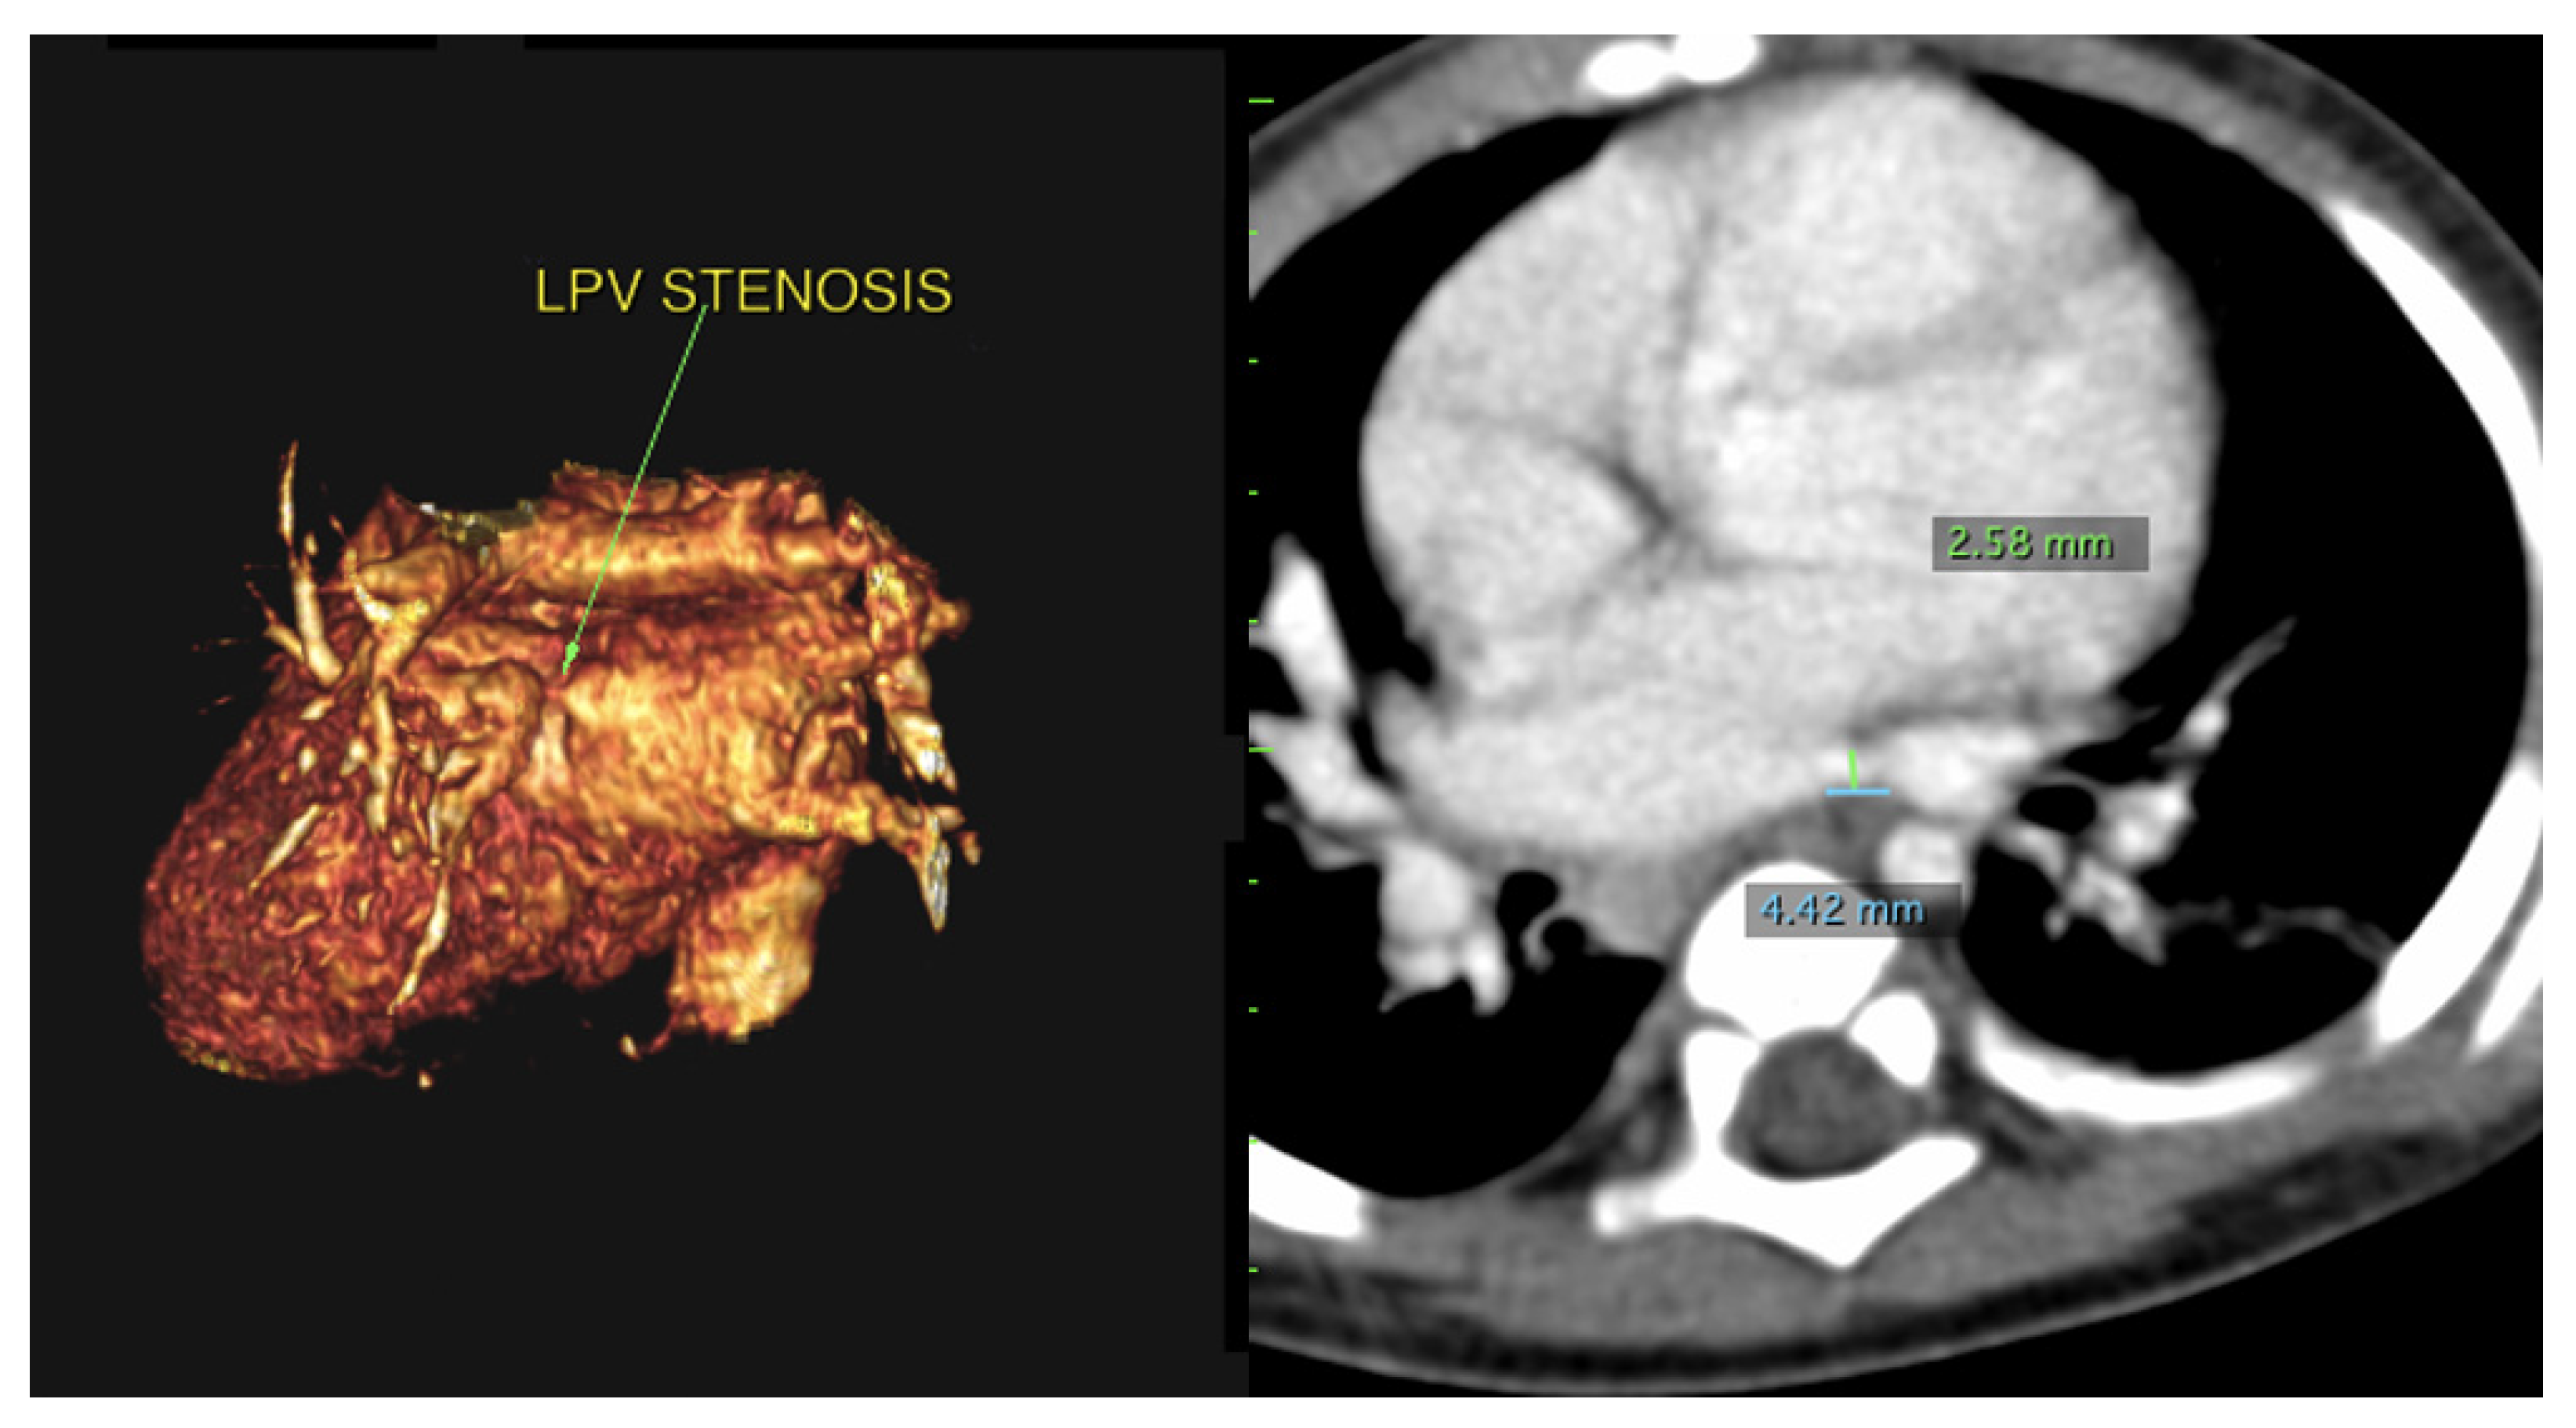

Using PVS as an initial search term, 57 cases from 24 different institutions were identified and included for analysis. Table 1 is a list of the institutions reporting cases of PVS and Figure 1 is a map of this. Figure 2 and Figure 3 are of a computed tomographic (CT) scans performed on described cases from Malaysia (Figure 2) showing repaired TAPVR with recurrent stenosis and Vietnam (Figure 3) showing idiopathic common left pulmonary vein stenosis.

Figure 3.

CT scans from the above described patient from Vietnam with left common pulmonary vein stenosis. The left image is a 3D reconstruction of a CT angiogram with the view of the left pulmonary vein connection to the left atrium. The arrow denotes the area of stenosis. The right image is a traditional CT angiogram with sternum anterior and spine posterior. The green marker is of the stenosis which narrows to 2.58 mm. The blue marker is of the length of the area of stenosis which is 4.42 mm.

“The patient was a 9-month-old who presented due to cough and shortness of breath. An echocardiogram revealed a small perimembranous ventricular septal defect (VSD) that was not hemodynamically significant and routine follow up was recommended. She continued to have respiratory difficulty at home and re-presented. A repeat echocardiogram re-demonstrated the VSD and showed left pulmonary vein stenosis. She was admitted for a CT which showed 2 left pulmonary veins to a common left pulmonary vein with stenosis at the common vein to left atrial connection. Right pulmonary veins were normal. She underwent VSD closure and sutureless anastomosis for left pulmonary veins 2 months later. The repair was delayed because of other urgent cases at the institution (Figure 3).”—Dinh Quang Le Thanh, MD, MS, Pediatric General and Cardiac Surgeon, Children’s Hospital 1, Ho Chi Minh City, Vietnam